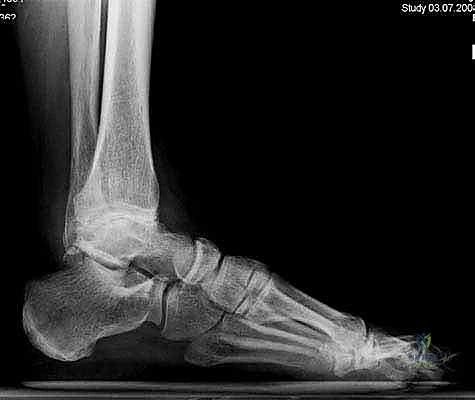

لفهم أهمية جراحة استبدال الكاحل، يجب أولاً فهم تشريح هذا المفصل المعقد. يتكون مفصل الكاحل من التقاء ثلاث عظام رئيسية:

1. عظمة الظنبوب (Tibia): وهي عظمة الساق الكبرى التي تشمل الجزء الداخلي والعلوي من الكاحل.

2. عظمة الشظية (Fibula): وهي عظمة الساق الصغرى التي تشكل الجزء الخارجي من الكاحل.

3. عظمة الكاحل (Talus): وهي العظمة السفلية التي ترتكز عليها عظام الساق وتعمل كمفصلة للحركة.

تُغطى نهايات هذه العظام بطبقة ناعمة ومرنة تسمى الغضروف المفصلي، والذي يعمل كوسادة لامتصاص الصدمات وتقليل الاحتكاك أثناء الحركة. عندما يتآكل هذا الغضروف، تبدأ العظام بالاحتكاك ببعضها البعض، مما يسبب ألماً مبرحاً وتورماً وتيبساً.

1. التهاب المفاصل بعد الصدمة (Post-Traumatic Arthritis)

وهو السبب الأكثر شيوعاً لتلف مفصل الكاحل. يحدث بعد سنوات من تعرض الكاحل لإصابة شديدة مثل الكسور المعقدة أو الالتواءات المتكررة التي أدت إلى تمزق الأربطة وعدم استقرار المفصل، مما يسرع من عملية تآكل الغضروف.

1. التقييم والتحضير قبل الجراحة

يتم إجراء فحوصات شاملة تشمل الأشعة السينية (X-rays)، والأشعة المقطعية (CT scan) لإنشاء نموذج ثلاثي الأبعاد لكاحل المريض. يساعد هذا د. هطيف في اختيار الحجم الدقيق للمفصل الصناعي وتحديد زوايا القطع بدقة متناهية.